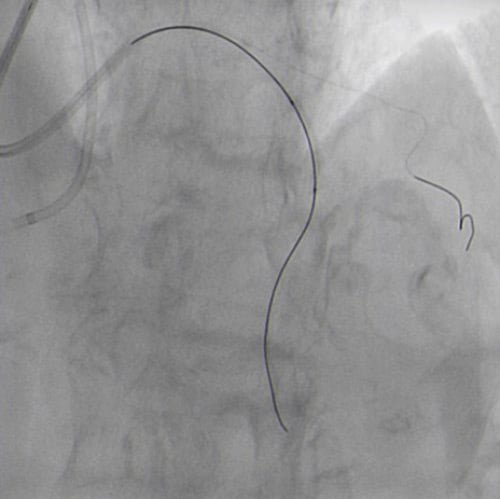

JR 4.0 guiding catheter exchanged with JL 4.0 to achieve left main (ping-pong) and position a parallel wire in left anterior descending (Figure 7.2). In the first wire we have the balloon, in the second wire a covered stent, but the perforation resolved only with balloon dilatation so we avoided, at this time to implant a covered stent.